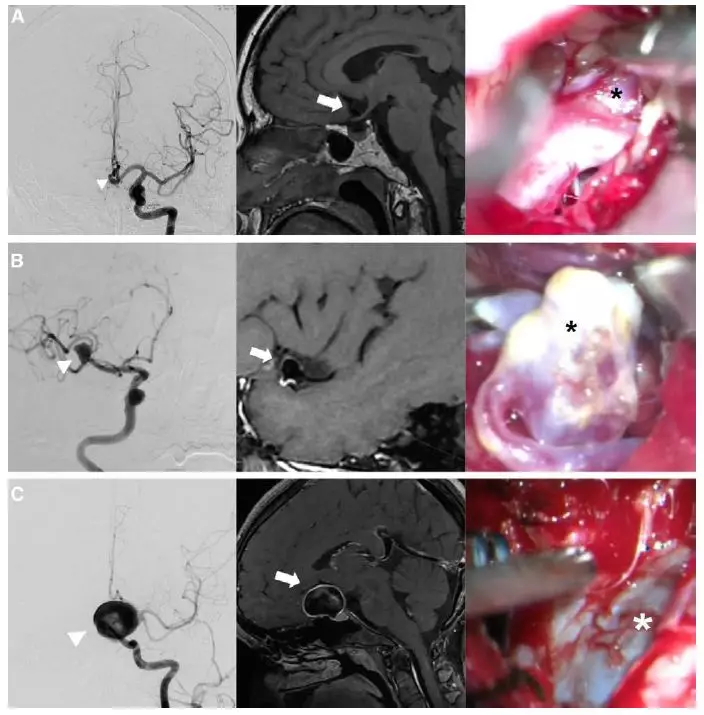

图1. 颅内动脉瘤的高分辨黑血磁共振强化信号三种分型及术中图片。A,前交通动脉未破裂动脉瘤,术前高分辨磁共振无强化。术中未见瘤壁滋养血管或动脉粥样硬化。B,中动脉未破裂动脉瘤,术前高分辨磁共振局部强化(FWE),术中可见对应强化的瘤颈部位大块粥样硬化斑块附着。C,巨大未破裂颈眼动脉瘤,术前高分辨磁共振均匀强化(UWE),术中见瘤体明显的滋养血管增生,但未见粥样硬化斑块。